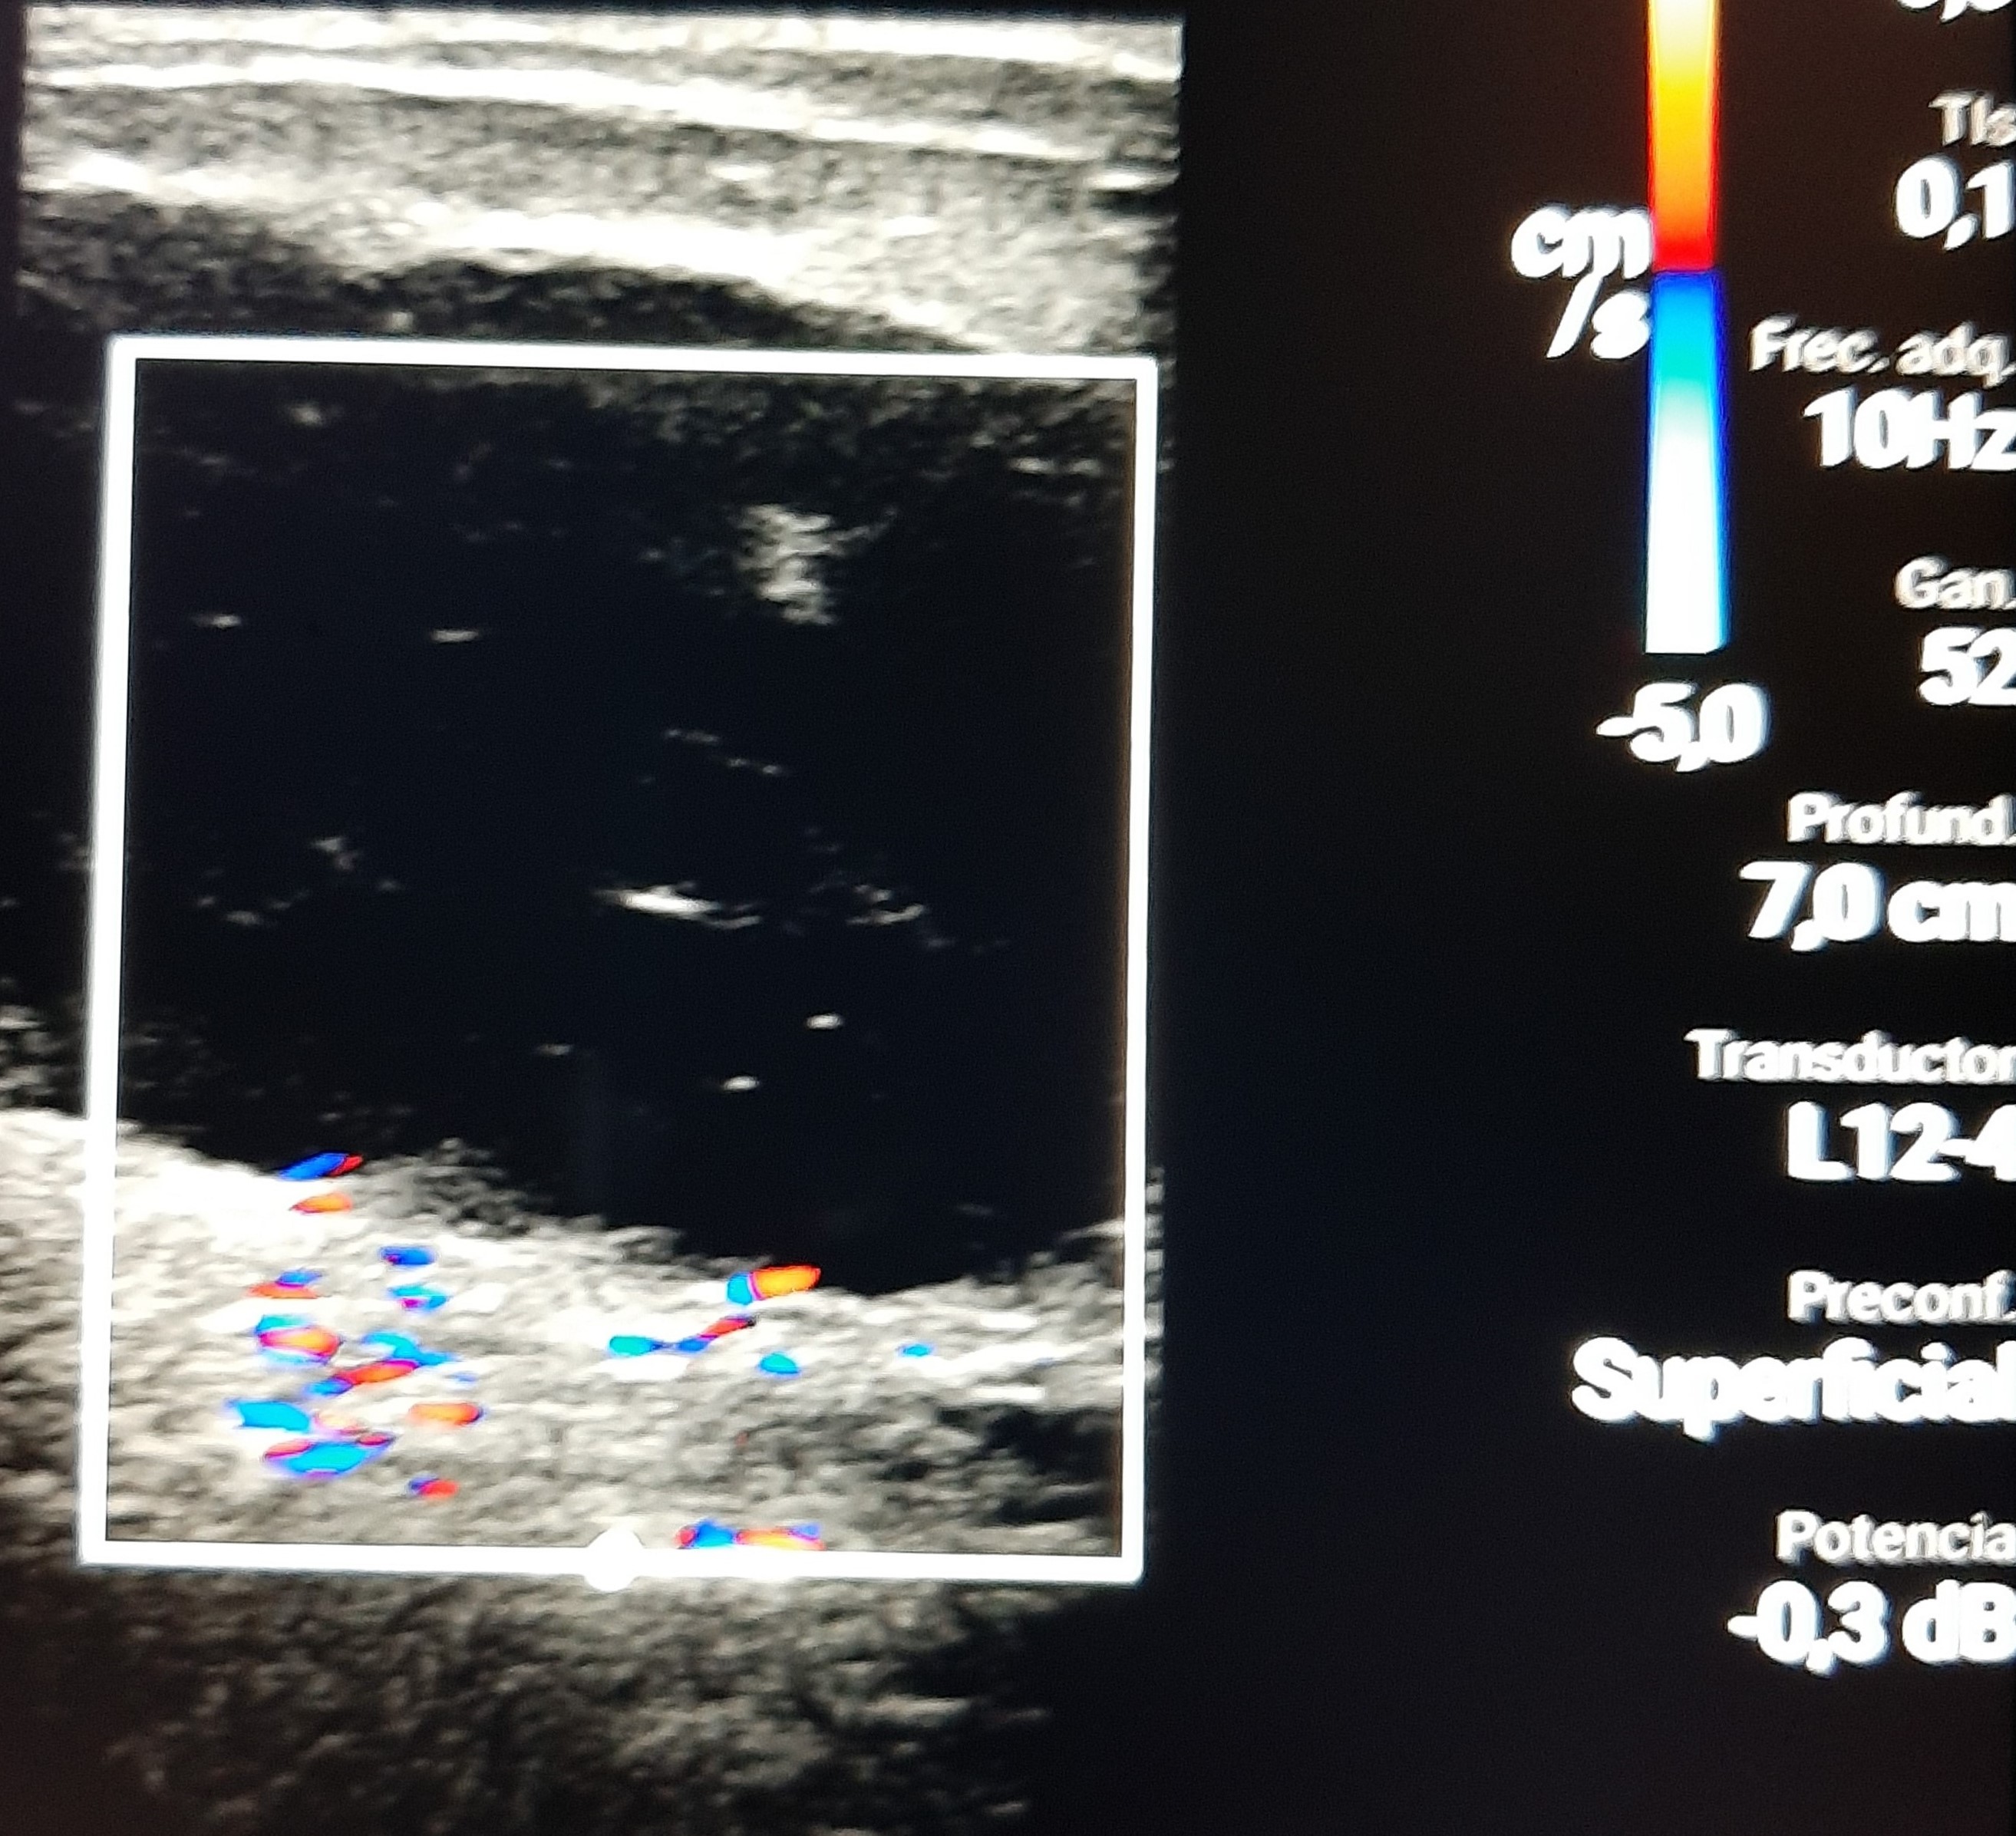

Hallazgos ecográficos

En la cama del paciente se explora con la sonda lineal el area indurada del abdomen encontrando una colección bien delimitada, hipoecogénica con áreas isoecogénicas irregulares en su interior, sin vascularización anómala en el doppler, apoyando así el diagnostico de Hematoma de la Vaina de los Rectos.